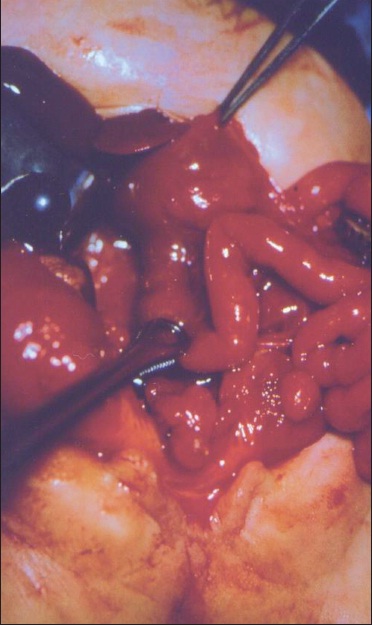

Vasundhara Tolia, MD; Sanjay Khubchandani, MD

A 9-year-old girl was seen in the emergency department (ED) with a 5-day history of non-bilious, non-projectile emesis, decreased appetite, and persistent right lower quadrant pain following an appendectomy...